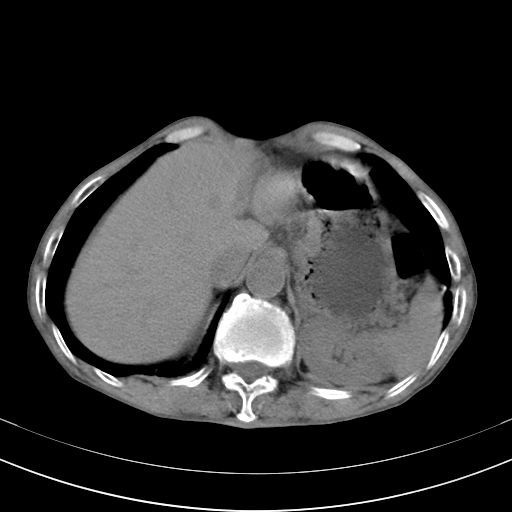

标题: 男,65岁,反复右上腹痛, [打印本页]

标题: 男,65岁,反复右上腹痛,

胃镜提示十二指肠占位